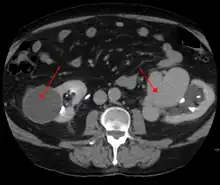

AVMs are diagnosed primarily by the following imaging methods:[12]

- Computerized tomography (CT) scan is a noninvasive X-ray to view the anatomical structures within the brain to detect blood in or around the brain. A newer technology called CT angiography involves the injection of contrast into the blood stream to view the arteries of the brain. This type of test provides the best pictures of blood vessels through angiography and soft tissues through CT.